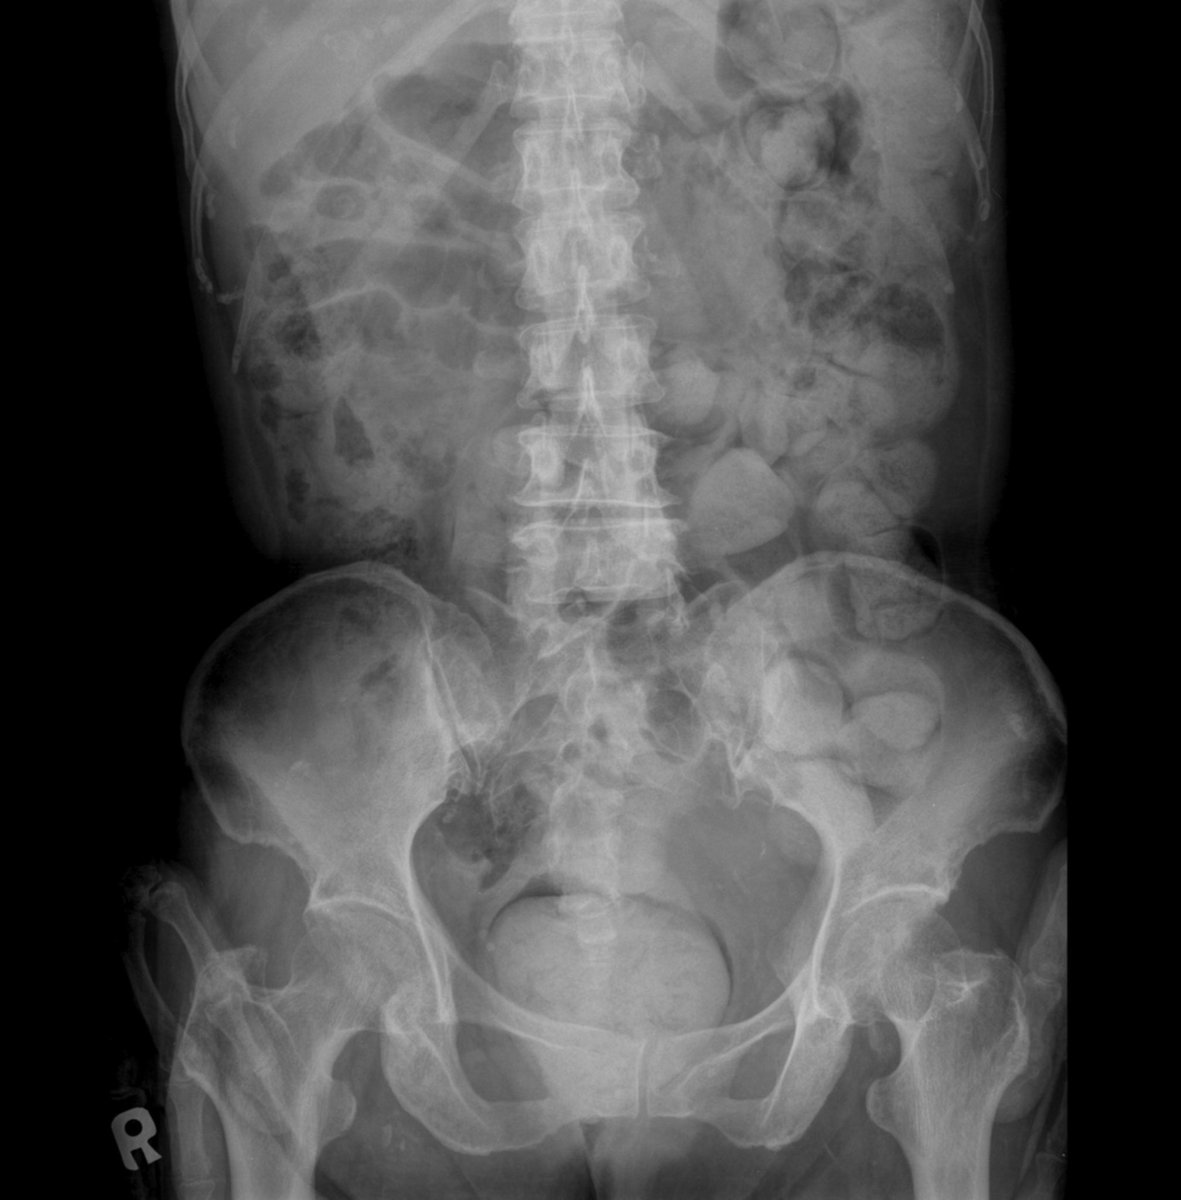

٢٤- ماذا اتوقع من زيارتي للطبيب ؟

سيتم اخذ معلومات معينة وعمل فحص سريري ومن ثم إجراء بعض الفحوصات المخبرية واذا لزم الأمر عمل انواع معينة من الاشعات للوصول إلى التشخيص ومن ثم البدء بالعلاج .. ١/٢

٢٥- في حالات معينة يتم طلب فحص للقولون باستعمال المنظار وكذلك كل شخص بلغ سن ال٤٥ فما فوق .. الغرض من ذلك هو الكشف المبكر عن أورام القولون والمستقيم ومعالجتها في مراحل مبكرة ( حمانا الله وإياكم من كل شر ومكروه ) ٢/٢